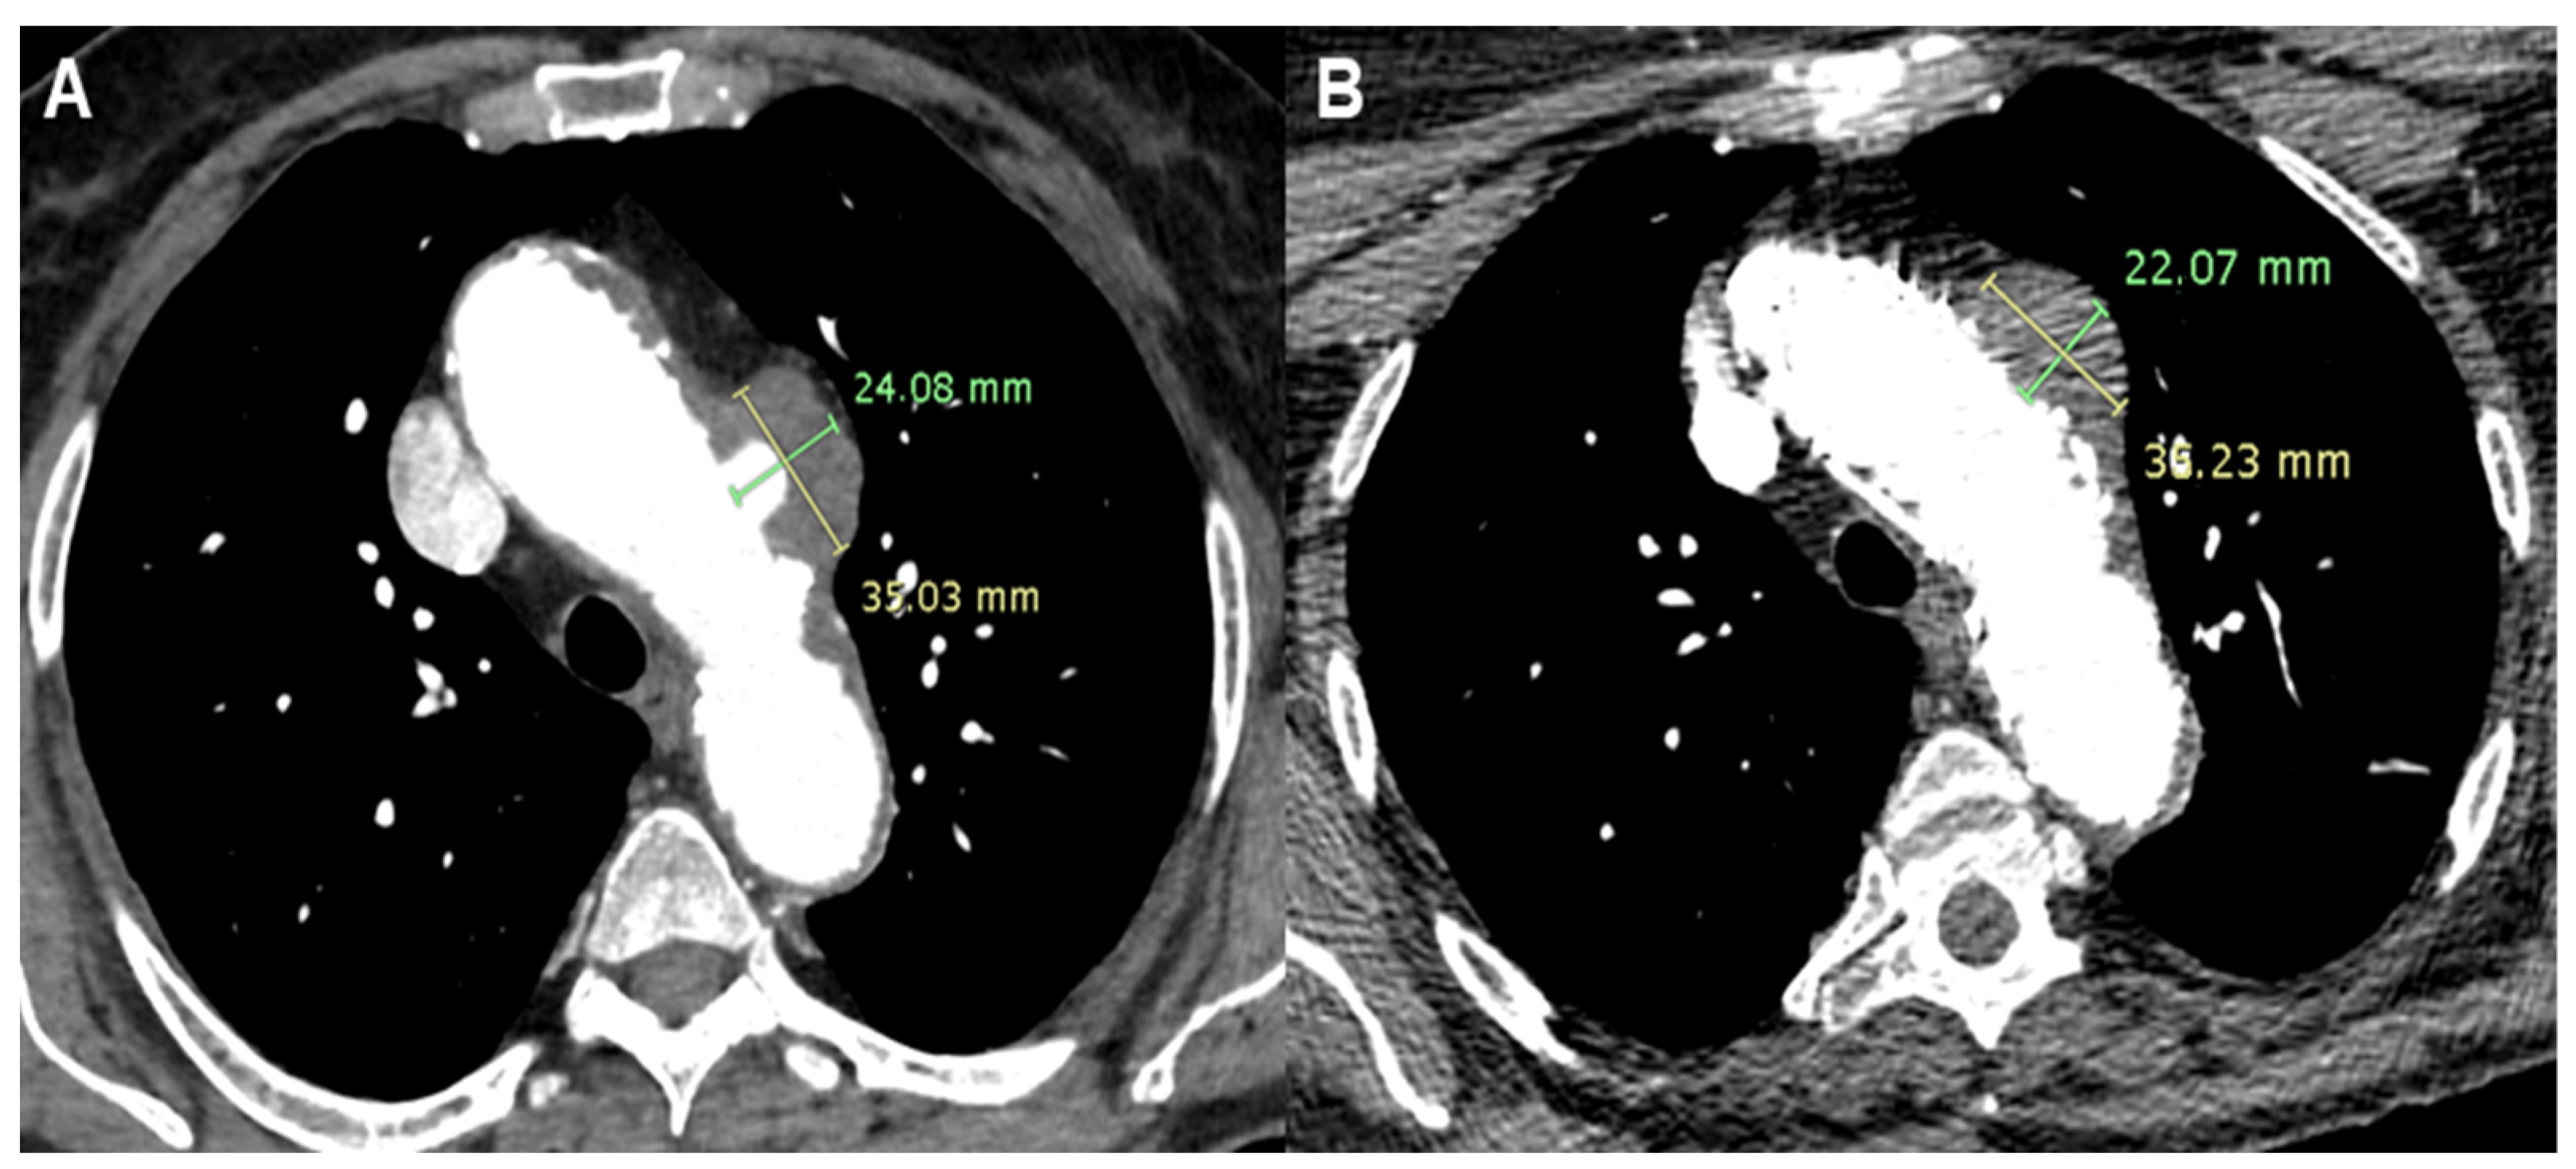

A 73-year-old lady presented to A&E with a sudden onset of chest pain radiating to the back in the context of hypertension, multi-nodular goiter, psoriatic arthritis, nephrolithiasis, and a history of deep vein thrombosis and pulmonary embolism. Computed Tomography Angiography (CTA) revealed a PAU with saccular pseudoaneurysm formation (24 × 35 mm) on the left aspect of the aortic arch. The position of the aortic lesion was not favorable, as it corresponded with the origin of the left carotid artery. Clinical presentation confirmed the sub-acute onset and progression of the pathology. Additionally, the patient was under follow-up for multi-nodular goiter, with a planned surgical treatment involving total thyroidectomy. Different strategies were considered, with open chest surgery deemed too risky for the patient. An alternative surgical approach involving the creation of supra-aortic branch bypasses and the placement of an endovascular aortic prosthesis could complicate the multi-nodular goiter surgery. Therefore, total endovascular treatment was considered the optimal strategy [4].

Following a period of clinical observation without further episodes of chest pain, a customized cone-shaped prosthesis was designed to accommodate the proximal aortic arch dilatation. It featured a scalloped design to fit the origin of the left carotid artery and included a fenestration for the left subclavian artery (Terumo, Custom Relay Plus 38-32 × 180 mm). A stent was placed at the origin of the left subclavian artery and inserted through the fenestration to ensure branch patency. Additionally, to ensure proper prosthesis adaptation and prevent potential type I endoleak formation, endovascular ballooning with transvenous rapid cardiac pacing was performed to seal the proximal end of the aortic prosthesis in Ishimaru Zone 1 (Figure 1).

Figure 1.

Patient 1’s Computed Tomography Angiography showing a Penetrating Aortic Ulcer (PAU) of the aortic arch (A) and the complete exclusion of the PAU after Thoracic Endovascular Aortic Repair (TEVAR) with reduction in the dimension of the pseudoaneurysm (B).